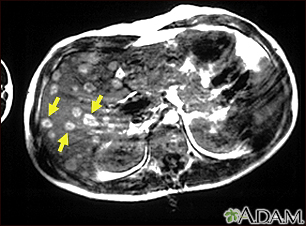

Melanoma of the liver - MRI scan

This upper abdominal MRI scan shows multiple tumors in the liver which have spread (metastasized) from a malignant melanoma in an arm or leg. Note the light circular areas throughout the liver (seen mostly on the left side of the screen).